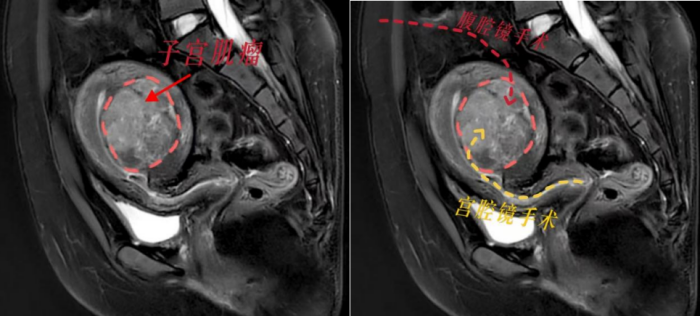

根据小丽的病情,我院妇产科三区副主任魏馨分析,宫腔镜手术无需腹部切口,通过自然腔道进行,切除肌瘤无需切开子宫肌层,能最大程度保护患者生育力。但是根据子宫肌瘤诊治专家共识,像小丽这样的病例并不适合宫腔镜手术,因为手术风险极高,难以一次性切除干净,还可能引发水中毒、子宫内膜损伤等严重并发症。而如果选择腹腔镜下子宫肌瘤剥除术,就必须把子宫肌层完全切开,术后至少需要等待1年才能怀孕,且怀孕后子宫破裂的风险极大。这对于渴望成为母亲的小丽来说,无疑是沉重的打击。

面对患者强烈的生育需求,魏馨主任带领团队迎难而上,决心挑战“不可能”!经过反复研究病情和推敲手术方案,魏馨主任凭借丰富的临床经验和精湛的宫腔镜手术技巧,成功为小丽实施了高难度宫腔镜下子宫肌瘤切除手术。手术不仅一次性将肌瘤彻底切除,而且没有损伤子宫肌层和内膜,术中出血少,术后恢复快,未出现任何并发症。术后第2天,小丽便顺利出院,术后3个月即可备孕,重燃了她成为母亲的希望。